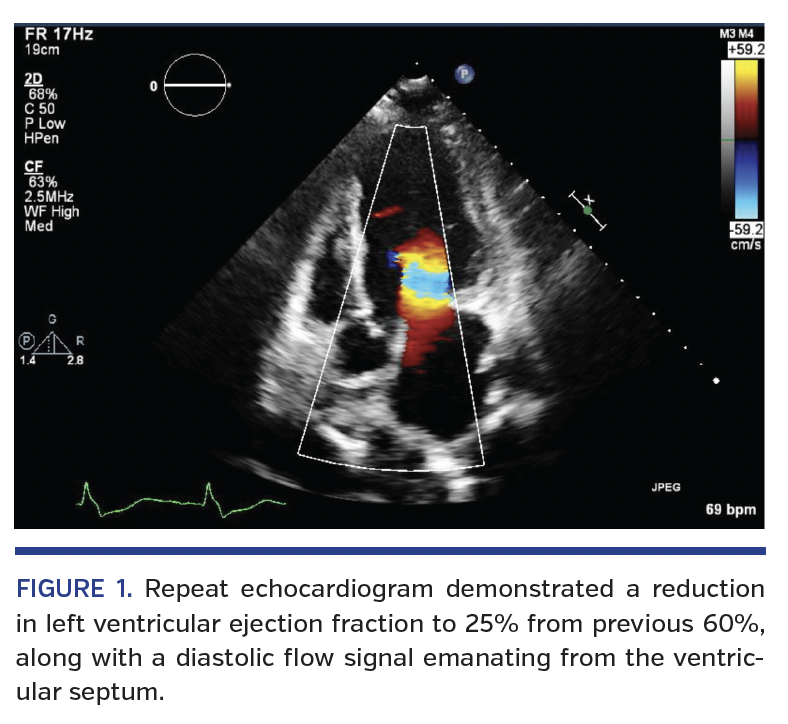

The patient is a 44-year-old woman with a history of HCM. She presented to our cardiovascular center 1 month after undergoing septal myomectomy for HCM along with repair of an apical aneurysm with thrombus evacuation; her surgery had been deemed a success, with reduction in left ventricular septal size from 30 mm to 8 mm and complete elimination of obstructive gradient. In the month after her surgery, she developed progressive exertional dyspnea, dependent edema, and orthopnea. She was admitted and a repeat echocardiogram demonstrated a reduction in left ventricular ejection fraction to 25% from a previous 60%, along with a diastolic flow signal emanating from the ventricular septum (Figure 1). The patient subsequently underwent coronary angiography. This demonstrated numerous CCFs involving the left anterior descending and first diagonal arteries (Figure 2), as well as the right posterior descending artery (Figure 3). No significant coronary artery disease was noted. No intervention was performed. The patient was subsequently started on neurohormonal blockade for newly diagnosed heart failure and discharged with referral to the Advanced Heart Failure service for continued care.